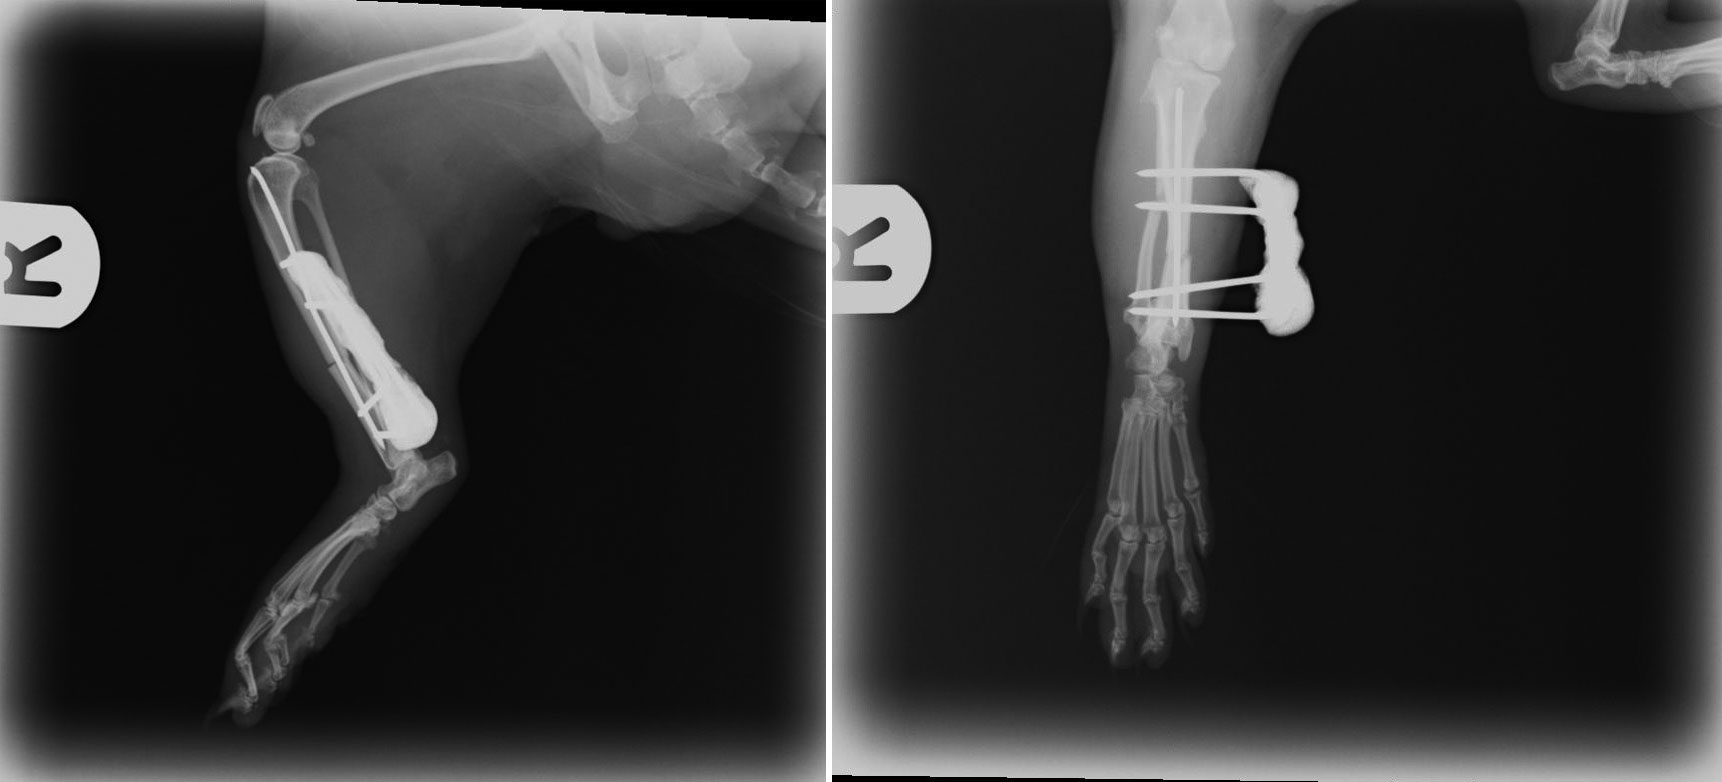

Jack Daniels (JD) is a ferret who came to see us in September with a very lame leg.

We x-rayed him and found that unfortunately he had broken his leg.

This presented us with quite the challenge because JD’s bones were so tiny. I performed an extremely fiddly operation to fix his bones back together again. Below you can see the x-rays we took after the operation - the white lines are tiny 1mm wide pins that are holding the two ends of bone together whilst the body heals them. The operation went extremely well and JD should make a full recovery.